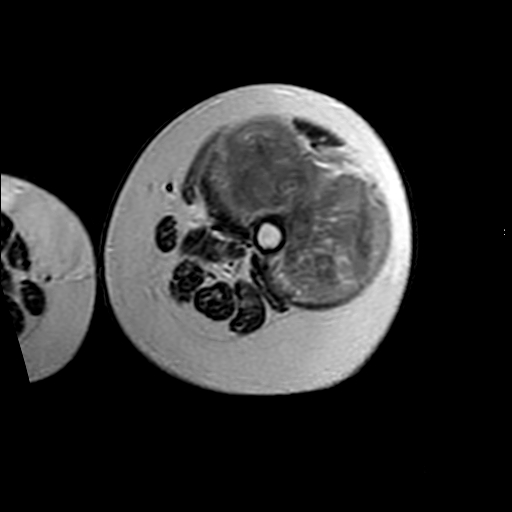

左侧大腿外伤10余年,当时情况不清,发现左侧大腿肿胀7年余,而后又有多次外伤史,近1年来出现疼痛,减重半年。查体:左侧大腿肿胀明显,皮温、肤色正常。

软组织肿块,股骨破坏,增强不均匀强化-----支持恶性肿瘤